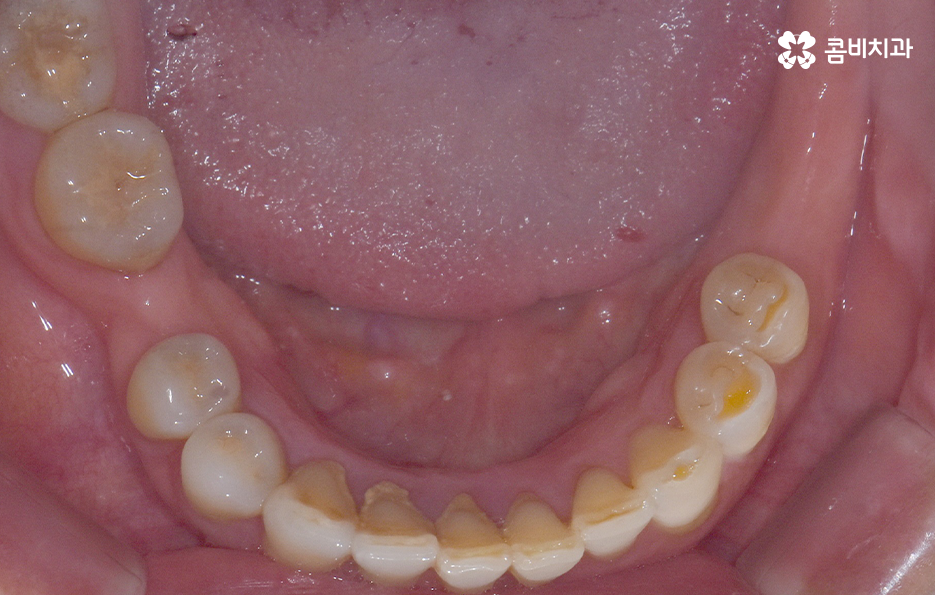

오늘 보시는 포스팅에서의 치료 과정도 어금니에 임플란트가 필요한 상태에서 윗니를 보시면 윗니가 다소 벌어진 것을 확인할 수 있는데요. 교정 하면 보통 전체교정을 떠올리게 되긴 하지만 경우에 따라서는 치열이 전체적으로 가지런한 편인데 앞니가 살짝 벌어진 경우나 어금니만 다소 벌어진 경우도 있을 거예요

이러한 경우에는 부분교정을 통해서 다소 개선이 필요한 치열을 가지런하게 만들고 가지런해진 치열과 교합 상태에 적합한 임플란트 치료 계획을 세워서 치아의 심미성과 기능적인 부분, 얼굴과의 조화를 종합적으로 고려하여 좋은 결과를 얻을 수 있어요